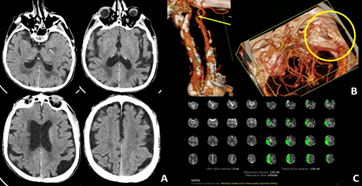

An 81-year-old man presented with left-sided hemiparesis and dysarthria upon awakening, consistent with a wake-up stroke. He had a history of coronary artery disease, previous minor stroke due to right carotid artery stenosis managed with endarterectomy and chronic peripheral vascular disease treated with an aortobifemoral bypass. Computed tomography (CT) showed no early signs of ischemia (Figure 1A), but demonstrated occlusion of the right internal carotid artery (ICA) along with distal occlusion of the middle cerebral artery (MCA) (Figure 1B). CT perfusion imaging revealed a large ischemic penumbra, estimated at 136 mL (Figure 1C). Diagnostic angiography was performed via puncture of the right aortofemoral graft (Figure 2A), confirming right ICA occlusion with poor collateral flow from the contralateral carotid circulation (Figures 2B-C). Severe calcified stenosis at the origin of the right common carotid artery (CCA) precluded mechanical thrombectomy (MT) via both femoral and radial access routes (Figures 2D-E).

Figure 1: CT showed no early signs of ischemia (A). CT angiography pointed out tandem occlusion of right ICA and distal M2 segment of MCA (yellow arrow and circle; B). No ischemic core was found on perfusion imaging (C).